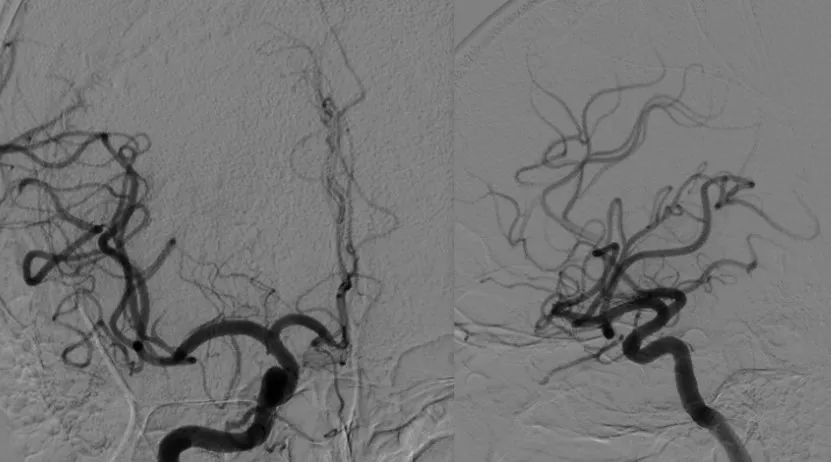

黄金波教授大脑中动脉分叉部solitaire双支架夹栓术再通一例